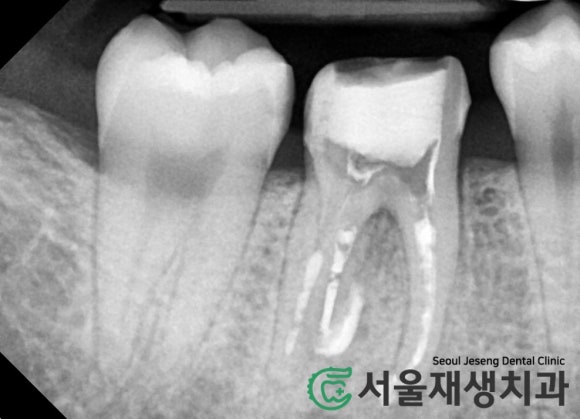

치아 뿌리 끝을 감싸는 동글동글하고

까만 빈 공간이 보이시나요?

바로 치근단염증입니다.

치근단염증(=뿌리염증)이란?

치아 뿌리 내에서 부패한 신경 조직들이

뿌리 끝의 조그마한 구멍을 통해 배출되어

뼈를 삭게 만드는 현상입니다.

치근단염증치료에 대한 경험이 부족하면

조금만 큰 치근단염증을 보더라도

급히 발치를 결정하게 될 수 있습니다.

대부분의 치과의사에게

다가가기 힘든 고난이도의 치료이기

때문이지요.